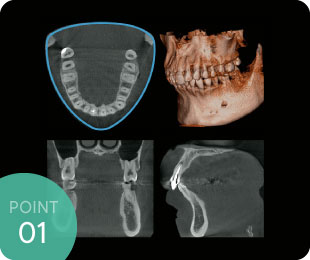

歯周病は歯を支えている顎の骨が溶けて(吸収して)いく病気ですので、歯周病が進行している場合、実際肉眼で見えている歯や歯ぐきと、中の骨の形態とはかなりのギャップがあります。

特に歯周再生療法(溶けた骨を再生させる手術)などの場合には3次元的に診断できることは手術の成功率に大きく影響します。

歯の根の形態は非常に複雑です。特に奥歯は根が2本以上あり、さらに1本1本の根の中にある神経の管も複雑な形態をしています。

2次元では見えなかった部分が3次元になることでしっかり把握でき、より正確な根管治療を行うことができるため、治療の精度や予後に大きな差ができます。

親知らずなどの抜歯においても神経・血管との位置関係も立体的に確認できるため、より安全に治療を行えます。